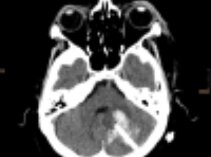

Intrazerebrale Blutung

Die intrazerebrale Blutung, also eine Blutung im Gehirn, tritt plötzlich auf und ist die schlimmste Form des Schlaganfalles.

Manchmal kann die Behandlung durch Evakuation mittels Operation oder Katheterpunktion mit Lysetherapie erfolgreich sein um die Stabilisierung des Patienten zu erreichen und um ein weiteres oder Nachbluten zu verhindern.

Wir bevorzugen – wenn notwendig und wenn möglich – die "bedside" Direktpunktion mittels Katheter und nachfolgende Lyse. Es ist eine minimal invasive, schnelle und effektive Behandlungsmethode.